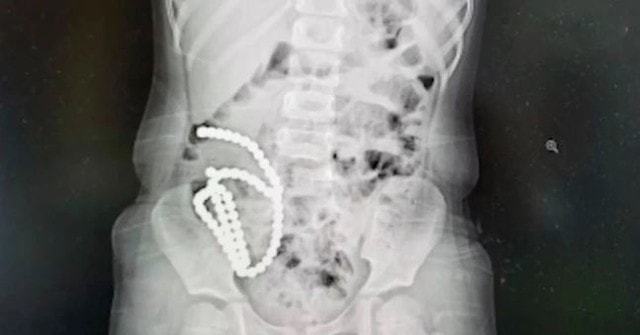

Bác sĩ Chen Qingjiang, Bệnh viện Nhi (Đại học Y khoa Chiết Giang), người điều trị chính, cho biết phim chụp X-Quang phát hiện có nhiều dị vật nhỏ có kích thước bằng hạt đậu nành trong bụng bé gái tên Xiaoyou, 4 tuổi. Dị vật này là những viên bi nam châm.

Với số lượng và mật độ của các hạt nam châm như thế, bệnh nhi phải trải qua 3 giờ phẫu thuật để loại bỏ vì các hình thức điều trị ít xâm lấn hơn sẽ không hiệu quả, bác sĩ Chen Qingjiang cho biết.

Các bác sĩ nghi ngờ cô bé đã nuốt những viên bi nam châm nhỏ nhiều lần. Sau khi đến các bộ phận khác nhau trong đường ruột, chúng hút vào nhau và gây ra các lỗ thủng.

"Sau khi tách các viên bi, chúng tôi phát hiện 14 lỗ thủng trong ruột của cô bé. Chúng tôi đã khâu lại và tất cả diễn ra suôn sẻ. Nhưng với cháu bé, ca mổ vẫn là một chấn thương lớn", bác sĩ Chen nói đồng thời cho biết thêm khả năng cao trong tương lai, bệnh nhi phải đối mặt với nguy cơ dính, tắc ruột.